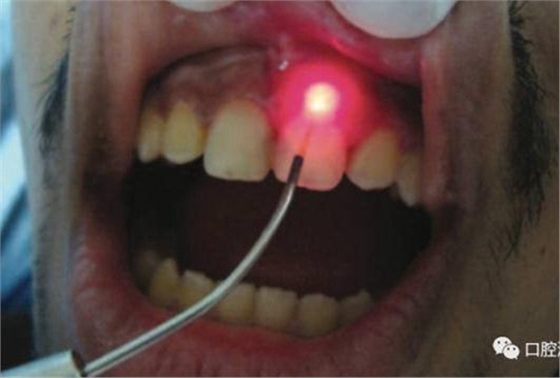

對瘺管位置進(jìn)行激光氣化

氣化消融發(fā)炎組織:利用高強度激光對根尖區(qū)域的腫脹、肉芽組織加熱使之氣化。如果發(fā)現(xiàn)有瘺管存在,可以將激光光纖插入瘺管中,采用間歇式發(fā)射激光的方式,邊發(fā)射激光,邊抽出光纖。此時務(wù)必注意激光功率不宜過高,而且光纖抽出速度不宜太慢或太快,以出現(xiàn)水汽為宜。